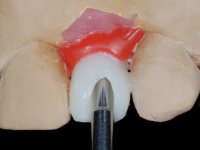

• Confection and bonding of a new feldspathic veneer to replace the fractured one. The new veneer should include a greater distal inter-proximal dental area from tooth 2.1.

• Replace tooth 1.2 veneer with a total crown in feldspathic ceramics, or by a now called 360 veneer.

The axis of insertion of the veneer in relation to the abutment was very carefully evaluated. The feldspathic veneers were prepared in the laboratory and then bonded to the mouth after placing absolute insulation. One year later, we began our third phase of treatment, after the veneer in tooth 2.1 fractured. A dental preparation was done on the bonded veneer, seeking to extend the distal inter-proximal interface more to the palate. The objective would be to move the veneer to a more palatine contact point. Preparation of tooth 1.2 was limited to creating an insertion axis. After preparation, the total crown and laboratory veneer were bonded to the mouth. First, the crown was bonded using a relative insulation with Teflon, later the veneer was bonded after the absolute insulation placement. In the crown, I used this type of insulation to avoid the use of staples. It would be difficult to apply due to the shape and size of the tooth, and would also be aggressive to the soft tissues. After bonding procedures, the occlusal integration of the work was evaluated.